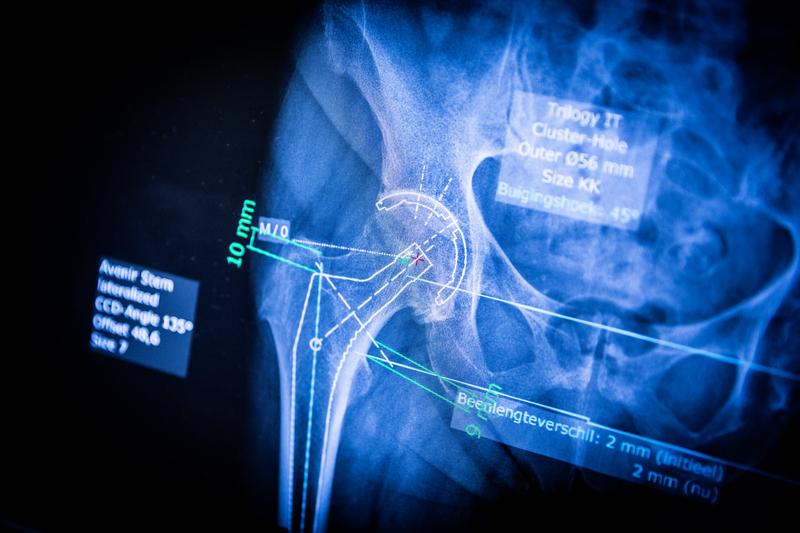

Moderne technieken

De medische wetenschap evolueert razendsnel. Als patiënt wil je daar de vruchten van plukken. In onze kliniek beschikken we over geavanceerde technologie voor de plaatsing van protheses. We gebruiken die technieken op een verantwoorde manier: alleen als ze een aantoonbare meerwaarde leveren voor jou. Je arts vertelt je welke techniek past bij jouw situatie.

Een knieprothese is een kunstknie. Bij een maatprothese wordt op basis van een scan gekeken hoe de prothese best gepositioneerd wordt volgens jouw specifieke anatomie.